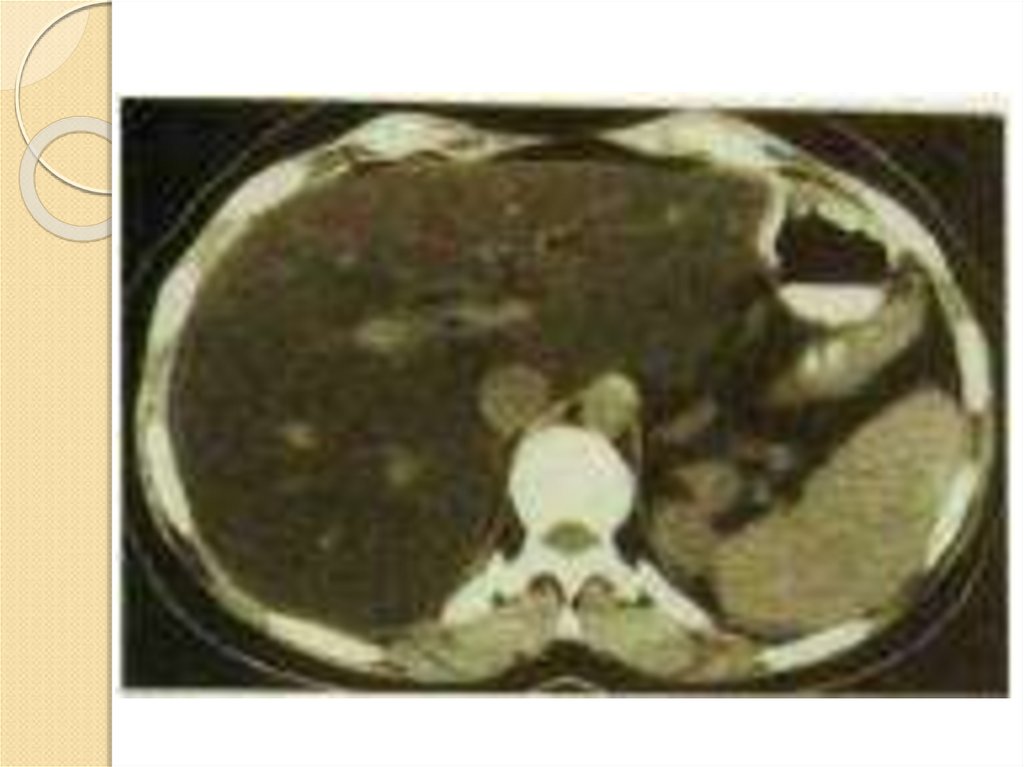

Компьютерная томограмма с контрастированием у больного

с жировой печенью. Резко снижен коэффициент поглощения

паренхимы, выделяются кровеносные сосуды.